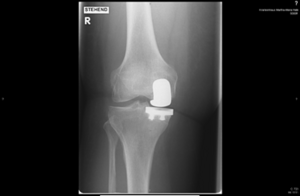

Am Kniegelenk werden sowohl der Teilflächenersatz (Schlittenprothese), der vollständige und auch der achstabilisierte Gelenkflächenersatz (gekoppelt) durchgeführt. Der stationäre Aufenthalt beträgt in der Regel acht bis zwölf Tage. Es schließt sich eine stationäre oder auch ambulante Rehabilitation von drei Wochen an.

Röntgenbild eines Kniegelenkersatzes, sichtbar im rechten Kniebereich.

Mediale Schlittenprothese Knie in 2 Ebenen

Kompletter Oberflächenersatz/Totalendoprothese Knie in 2 Ebenen